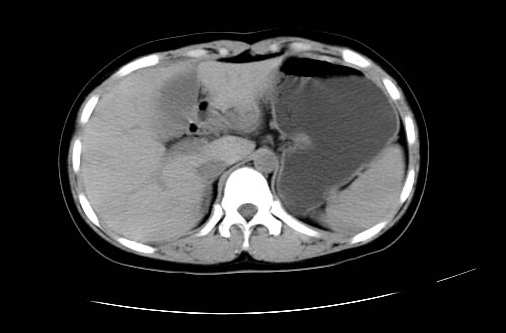

女 16岁  右上腹痛一天,无其他不适

肿块最大径位于十二指肠降段与水平段移行处,并且与肝脏压迹呈“0”形征,可以考虑位于肝外并与胃肠道关系紧密,考虑胃肠道间质瘤(gist)可能较大,须除外神经节起源肿瘤。

肿块与十二指肠关系密切,支持间质瘤诊断.肝脏与结肠均为受压改变.

右下腹巨大肿快,密度不均匀,内见坏死低密度区,边界清楚,与周边胀器明显有分界,未见强化,多考虑来源于间叶组织的良性肿物.

我坚决反对您的观点,该病例定位:横结肠肝曲与升结肠之间的肠系膜及部分肠壁。请看下图:

病灶巨大,少部分向肠腔内生长,大部分向长腔外生长。其密度不均匀,增强显示明显不均匀强化,并见有大片状始终不强化的不规则坏死液化区。虽然病灶中上部形态尚可,病人又如此年轻,但中下部形态、密度、强化特点强烈提示为恶性病灶。综上,我考虑本病例为:恶性胃肠道间质瘤。